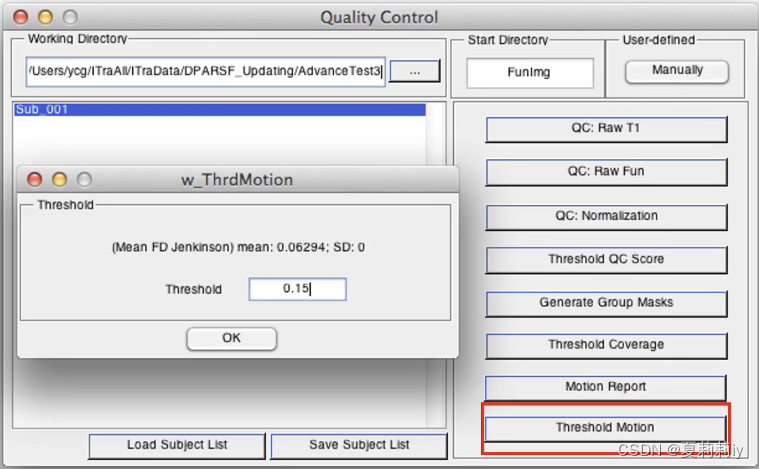

(9)Threshold Motion

①被试的平均值和被排除的阈值设置

(10)最后会生成一个SubjectList把所有不合格的被试都排掉